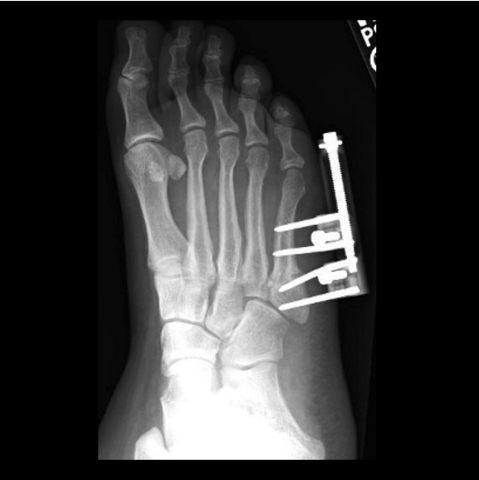

Figure 5a

Figure 5a. The 24-year-old required hardware removal and application of external fixation for gradual compression. Most cases heal within 6 weeks with gradual compression weekly.

-

Figure 5b